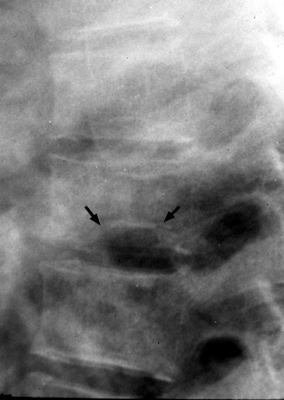

Lateral radiograph of the spine reveals central endplate depression with sparing of the anterior and posterior margins of the endplate. Several current names have been ascribed to these same changes seen in patients with hemoglobinopathy, such as Lincoln Log Sign, or H-shaped vertebra. Although not pathognomonic, these terms are typically reserved for a patient with Sickle-Cell disease.